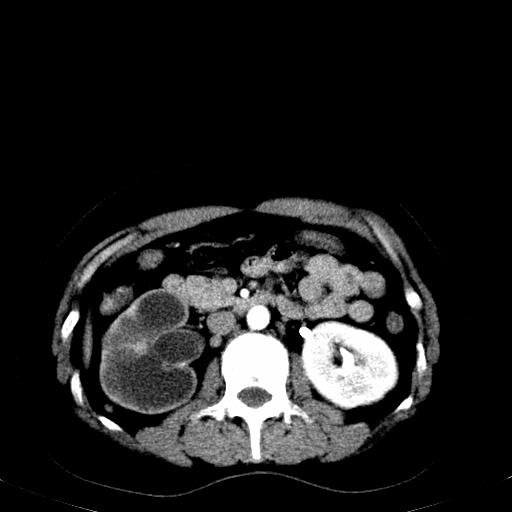

右肾多发囊肿,左肾、左输尿管结石

右肾重度积水,以肾盏积水明显,有分隔,上段输尿管轻度扩张,管壁增厚,考虑肾结核可能,请结合尿检查,胸部拍片排除肺结核。

右侧肾积水、左侧肾结石  ,要排除右肾结核可能。

右肾重度积水,建议ct向下扫描或逆行造影,左肾及左输尿管结石 .

要排除右肾结核可能

右肾积水、左侧肾脏结石,建议进一步检查原因除外左肾结核可能